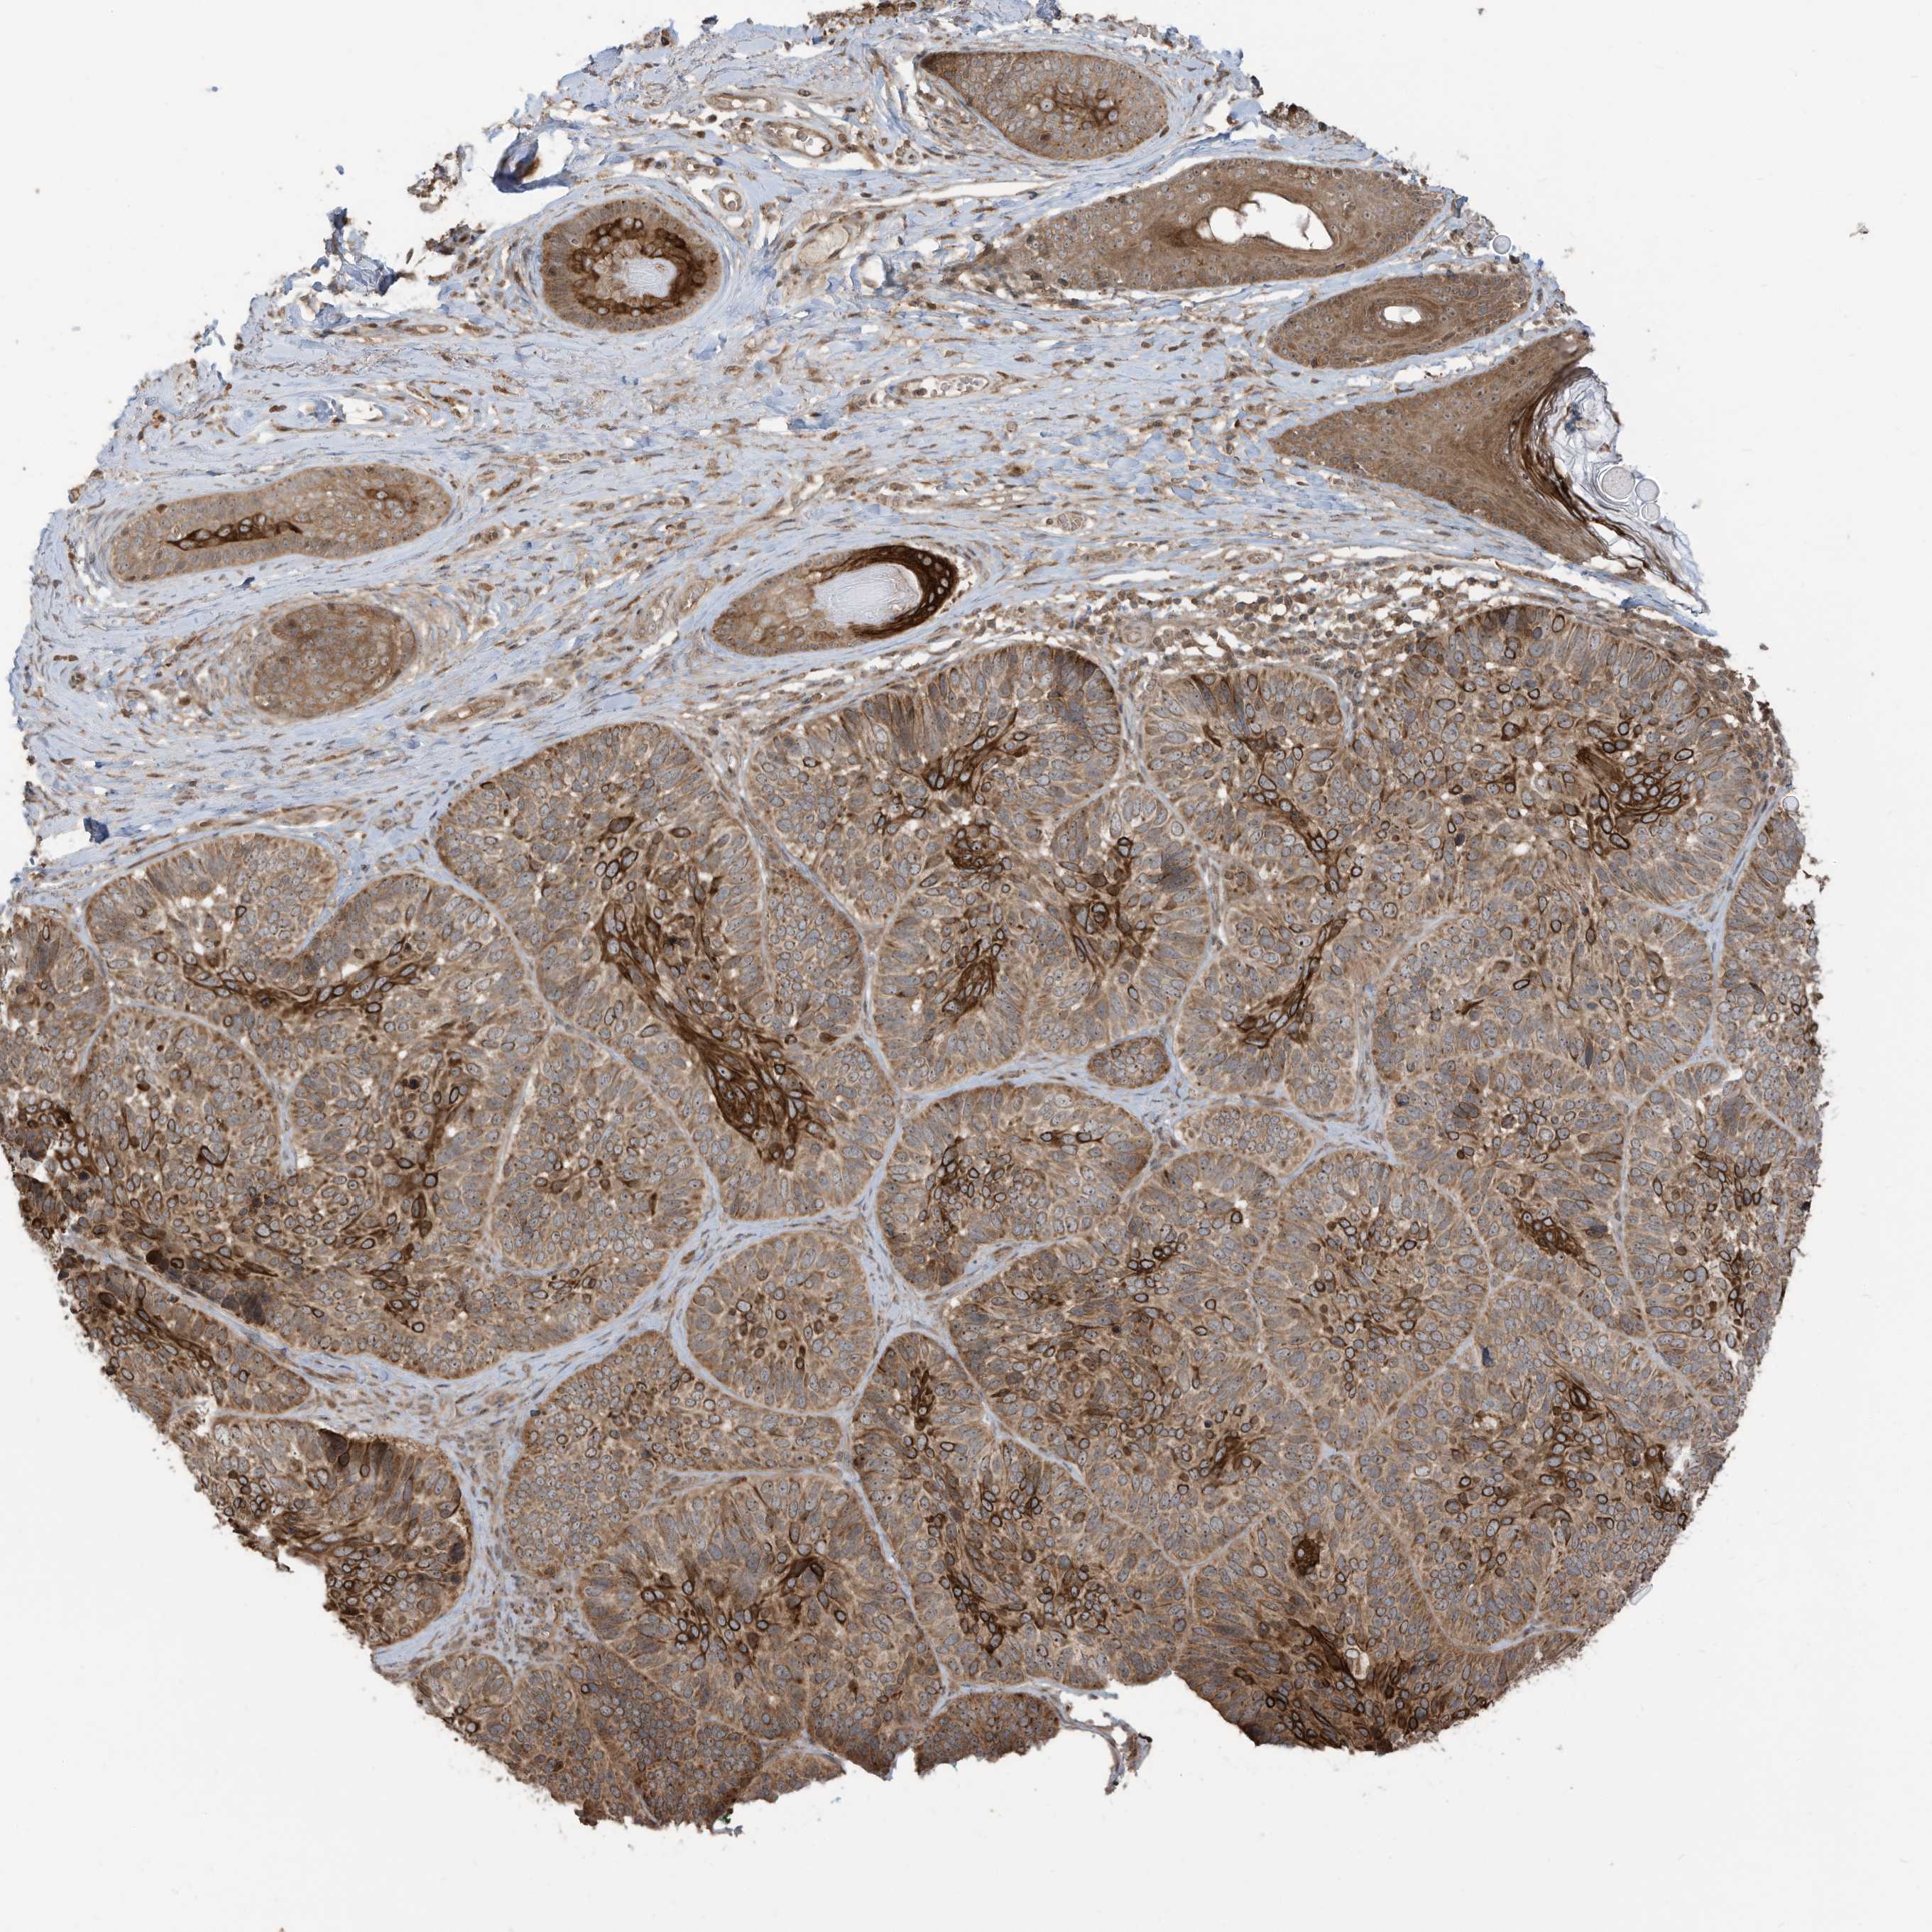

SKIN CANCER - Protein expressioni

A mouse-over function shows sample information and annotation data. Click on an image to view it in a full screen mode. Samples can be filtered based on level of antibody staining by selecting one or several of the following categories: high, medium, low and not detected. The assay and annotation is described here.

Each image is clickable and will lead to virtual microscopy that enables deeper exploration of all samples and also displays staining intensity scores, fraction scores and subcellular localization as well as patient and tissue information for each sample.

Antibody HPA034557

Staining

High

Intensity

Strong

Quantity

>75%

Location

Nuclear

Squamous cell carcinoma, metastatic, NOS